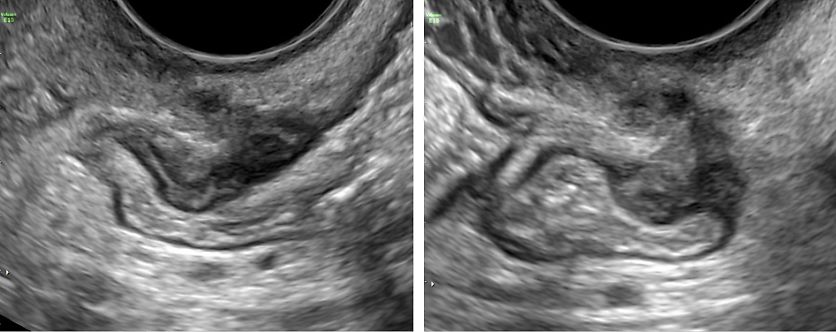

26

Ultrasound images of endometriomas with typical features of ground-glass echogenicity, up to four locules and no solid components.